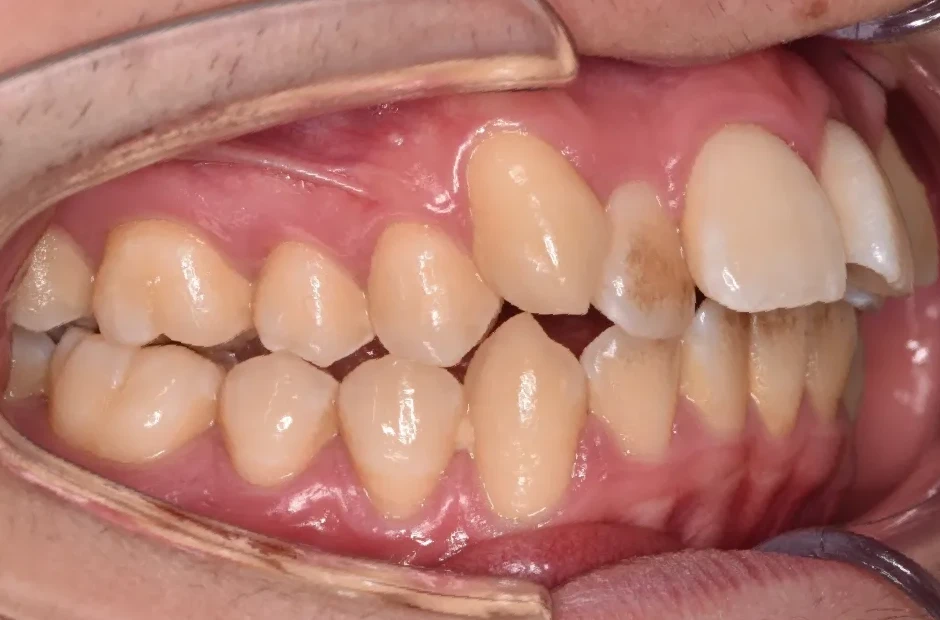

出っ歯

| 診断名・主訴 | 出っ歯 |

|---|---|

| 年齢・性別 | 16歳・男性 |

| 治療期間・回数 | 1年4か月 |

| 治療に用いた主な装置 | ブラケット |

| 抜歯部位 | 上顎4,4 |

| 治療費 | 60万円(税抜) |

| リスク・副作用 | 装置による違和感・疼痛・歯肉退縮・歯根吸収・虫歯のリスクなど |

治療前